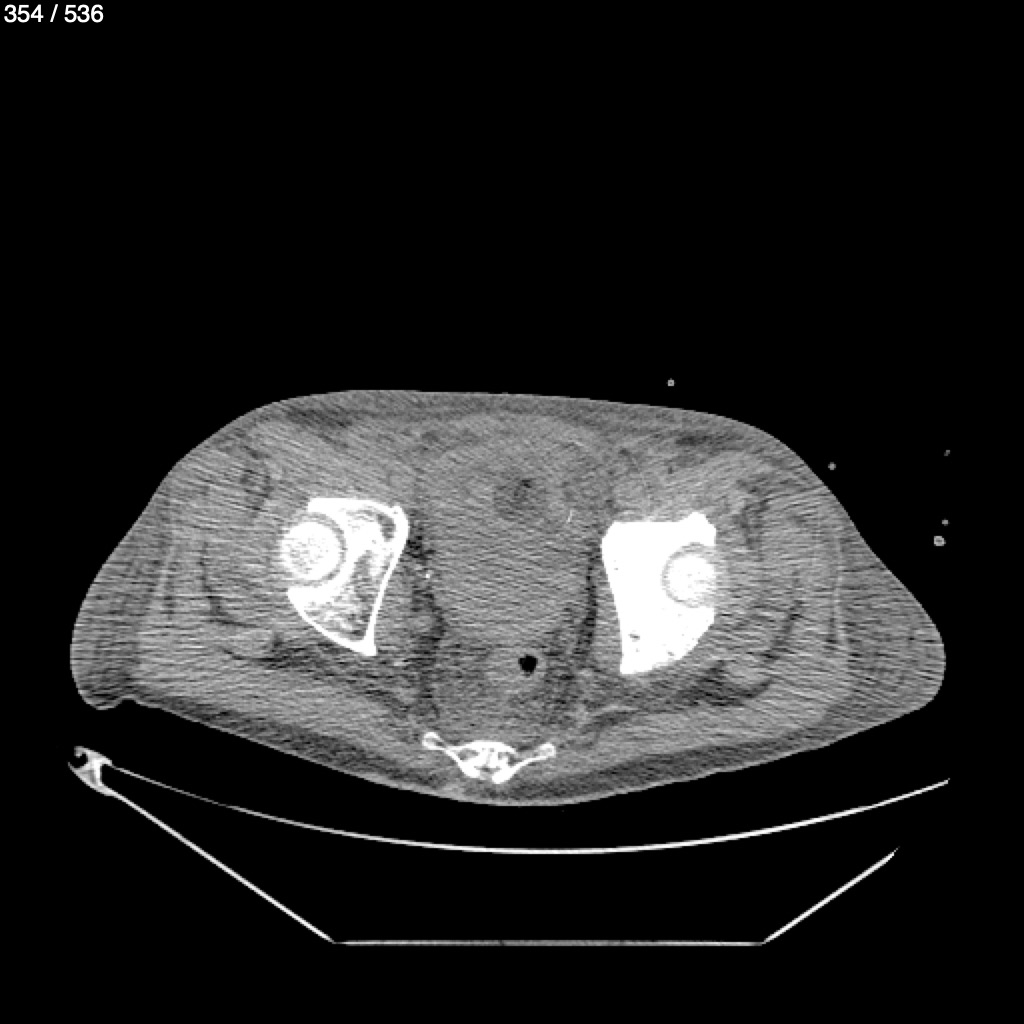

Angel Villalobos Palomeque 73 A - T.C Abdomen Simple